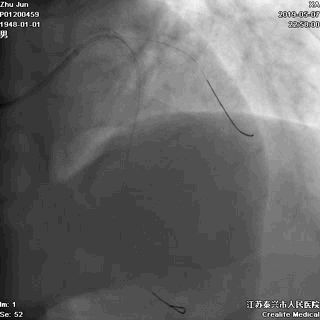

四、STENT植入

---巩固胜利成果

前降支植入第一枚STENT

前降支-左主干STENT定位和植入